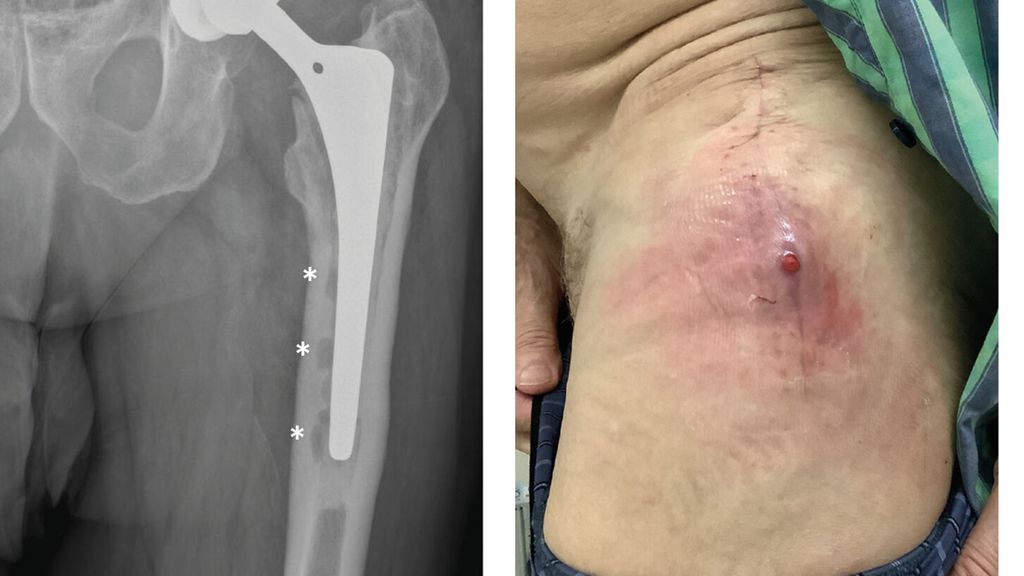

Die periprothetische Infektion (PPI) stellt eine der gefürchtetsten Komplikationen im Bereich der Orthopädie und Traumatologie dar. Sie ist verbunden mit hohen Morbiditäts- und ...

Mit zunehmendem Alter steigt die Rate an dislozierten medialen Schenkelhalsfrakturen. Meistens wird ein zementfreier oder zementierter Langschaft verwendet, seit Längerem werden auch ...